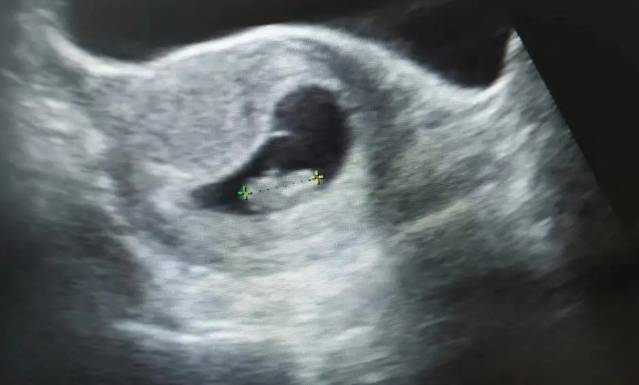

正常情况下,孕9周胎芽一般2.5cm为正常现象。这个时候要看胎心有无搏动,一般来说九周是有胎心搏动,如果检查正常可以到医院建卡。依据孕周的公式分别是孕周=孕囊最大径(cm)+3,妊娠龄(d)=胚长(mm)+42,孕9周孕囊大小标准值是6cm左右,孕9周胎芽大小标准值是1.2cm左右。而孕早期孕囊大小及胎芽大小不一定是标准值,可能偏大或者偏小,时间在一个星期以内都是正常现象,不必过于担心。